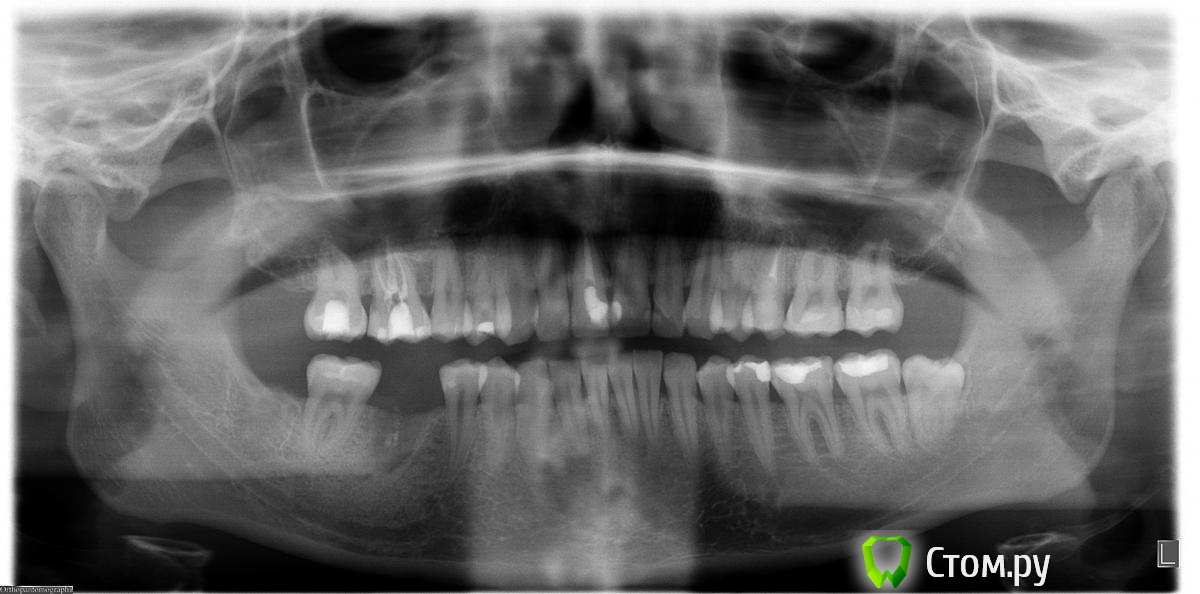

Юлия Арт Опубликовано 13 марта, 2014 Поделиться Опубликовано 13 марта, 2014 Здравствуйте! я совершенно в растерянности...около месяца назад мне сделали снимок верхних коренных, и врач увидел там большое воспаление-кисту у пятого зуба. сказал что она находится вбоку, а зуб депульпирован, возможно, с трещиной и надо удалять...месяц я себя настраивала, сделала - таки запись в госпиталь к хирургу, и сегодня там была... Хирург отправил меня на панорамный снимок, посмотрел и сказал не понимает почему меня к нему на удаление зуба послали - воспаления, говорит, нет, зуб нормальный, иди домой...я в шоке до сих пор-что это было?выкладываю фото " с кистой" в феврале и фото сегодня всей челюсти. Пожалуйста, прокомментируйте Ссылка на комментарий

Гарриевич Опубликовано 13 марта, 2014 Поделиться Опубликовано 13 марта, 2014 (изменено) мое мнение такое, очаг разрежения рисунка костной ткани в области 2.5 зуба с медиальной стороны есть. Зуб нужно перелечивать под микроскопом для того, чтобы запломбировать это боковое ответвление. Удалять зуб не надоPS на ОПТГ таких таких очагов может быть не видно, в следствии наложения позвонков, ключиц, сережек и пр. Изменено 13 марта, 2014 пользователем Гарриевич Ссылка на комментарий

Mane Опубликовано 13 марта, 2014 Поделиться Опубликовано 13 марта, 2014 На прицельном снимке виден воспалительный процесс. На понарамном - нет. "Киста" никуда не делась. Просто на панорамном снимке ее не видно. Такой снимок. Нужно сделать КТ (компьютерную томографию) и дать нам посмотреть. Мы и определим возможную причину. Если болит- решайте вопрос быстрее. Если трещина/фрактура корня - зуб на удаление. Если просто пропустили канал- перелечиваете и все будет хорошо. 2 Ссылка на комментарий